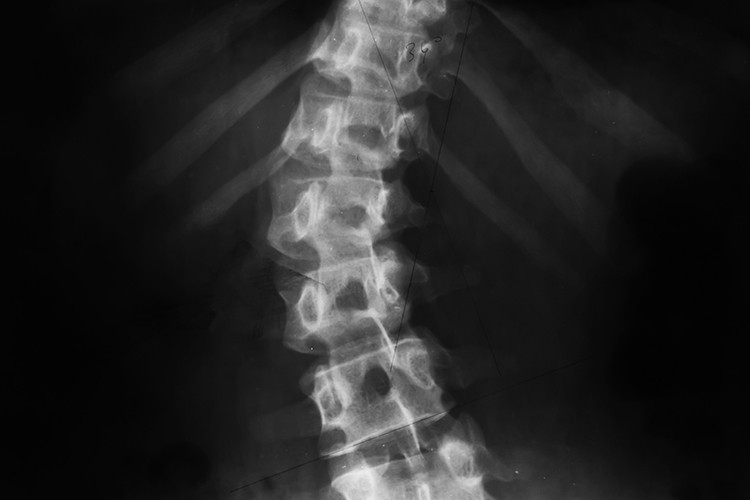

Ülkemizde her 10 çocuktan 1'inde skolyoz görüldüğünü belirten Fizik ve Rehabilitasyon Uzmanı Doç. Dr. Gülis Kavadar, hastalığı “Genel olarak omurganın sağ veya sola doğru 10 dereceden fazla eğriliği ile birlikte, aslında omurganın üç boyutlu bir şekil bozukluğudur” şeklinde tanımladı.